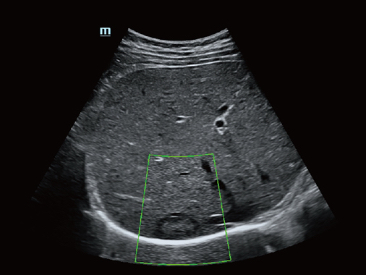

Fin dalla sua fondazione Mindray esplora continuamente nuovi modi per migliorare l'affidabilit├Ā diagnostica. Equipaggiata con la pi├╣ rivoluzionaria tecnologia ZONE Sonography?, la nuova piattaforma ZST+ di Resona 7 porta la qualit├Ā dell'immagine ecografica ad un livello superiore con l'acquisizione per zone e l'elaborazione dei dati canale.

Oltre alla qualit├Ā delle immagini di livello eccellente, Resona 7 migliora anche le capacit├Ā di ricerca clinica il rivoluzionario V Flow per la valutazione emodinamica vascolare, e l'acquisizione piani pi├╣ intelligente dal set di dati 3D per la diagnosi del sistema nervoso centrale fetale. Combinando il pi├╣ intuitivo funzionamento multi-touch basato su gesti e tutte le caratteristiche cliniche essenziali, Resona 7 sta veramente portando nuove tendenze nellŌĆÖinnovazione dellŌĆÖecografia.